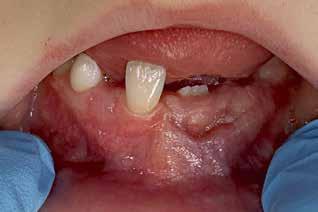

PATIENTTILFÆLDE 1

Patienttilfælde 1 (Fig. 1) er en 37-årig kvinde, henvist efter succesfuld behandling af stadie 3-parodontitis. Der er nu sundt

Før behandling

parodontium, ingen pocher over 4 mm, og både blødnings- og plakindeks er under 10 %. Patienten er motiveret for ortodontisk behandling, da hendes tænder er vandret over tid, delvist som følge af reduceret parodontium.

Der ses anterior trangstilling i begge kæber og overerupterede 1+1 og 2,1-1,2, hvilket resulterer i dybt bid med 2- tæt på ganepåbidning. Der er normale sidetandsrelationer, men der ses 5 mm horisontalt overbid (HOB) og 7 mm vertikalt

overbid (VOB). Papillen mellem 1+1 er betydeligt reduceret pga. fæstetab, og de mesialt kippede 1+1 har resulteret i en ”dark triangle”. Den facioorale funktion er for nuværende i.a. Panoramarøntgen (Fig. 1, I) viser marginalt knogletab i begge kæber og fravær af 8,7+7,8 og 8,7-8.

Objektivt anbefales behandling af det dybe bid, som ubehandlet forventes at forværres yderligere over tid. Patienten har ønske om behandling med æstetisk ortodontisk apparatur, alignere, og det vurderes muligt at behandle malokklusionen med alignere. Dog anbefales det generelt, at alignere undgås eller benyttes med væsentlige modifikationer af alignerens retention ved tandmobilitet, da dette ellers kan medføre jiggling, når aligneren tages af og på mange gange dagligt. På den anden side er der nogen evidens for, at alignerbehandling er associeret med bedre renhold og parodontal sundhed sammenlignet med fast apparatur (16).

Der planlægges alignerbehandling af begge kæber med intrusion af 1+1 og 2,1-1,2, nivellering af trangstilling UK med interproksimal reduktion (IPR) (Fig. 2 A, B) og senere IPR OK for reduktion af dark triangles mellem incisiverne efter nivellering. Patienten instrueres i at benytte alignere 20-22 timer/ dag med alignerskift hver 7. dag, og patienten ses hver 3.-8. uge under forløbet. Den første alignerserie består af 16 alignere for nivellering OK/UK og IPR i UK (Fig. 2). Efter denne serie planlægges IPR mellem incisiverne i OK for reduktion af dark triangles (Fig. 3) samt yderligere intrusion af OK og UK-fronten i 12 refinement-alignere. Patienten udviser god kooperation og er meget tilfreds med alignerapparaturet, som er mindre synligt end det faste apparatur (Fig. 4).